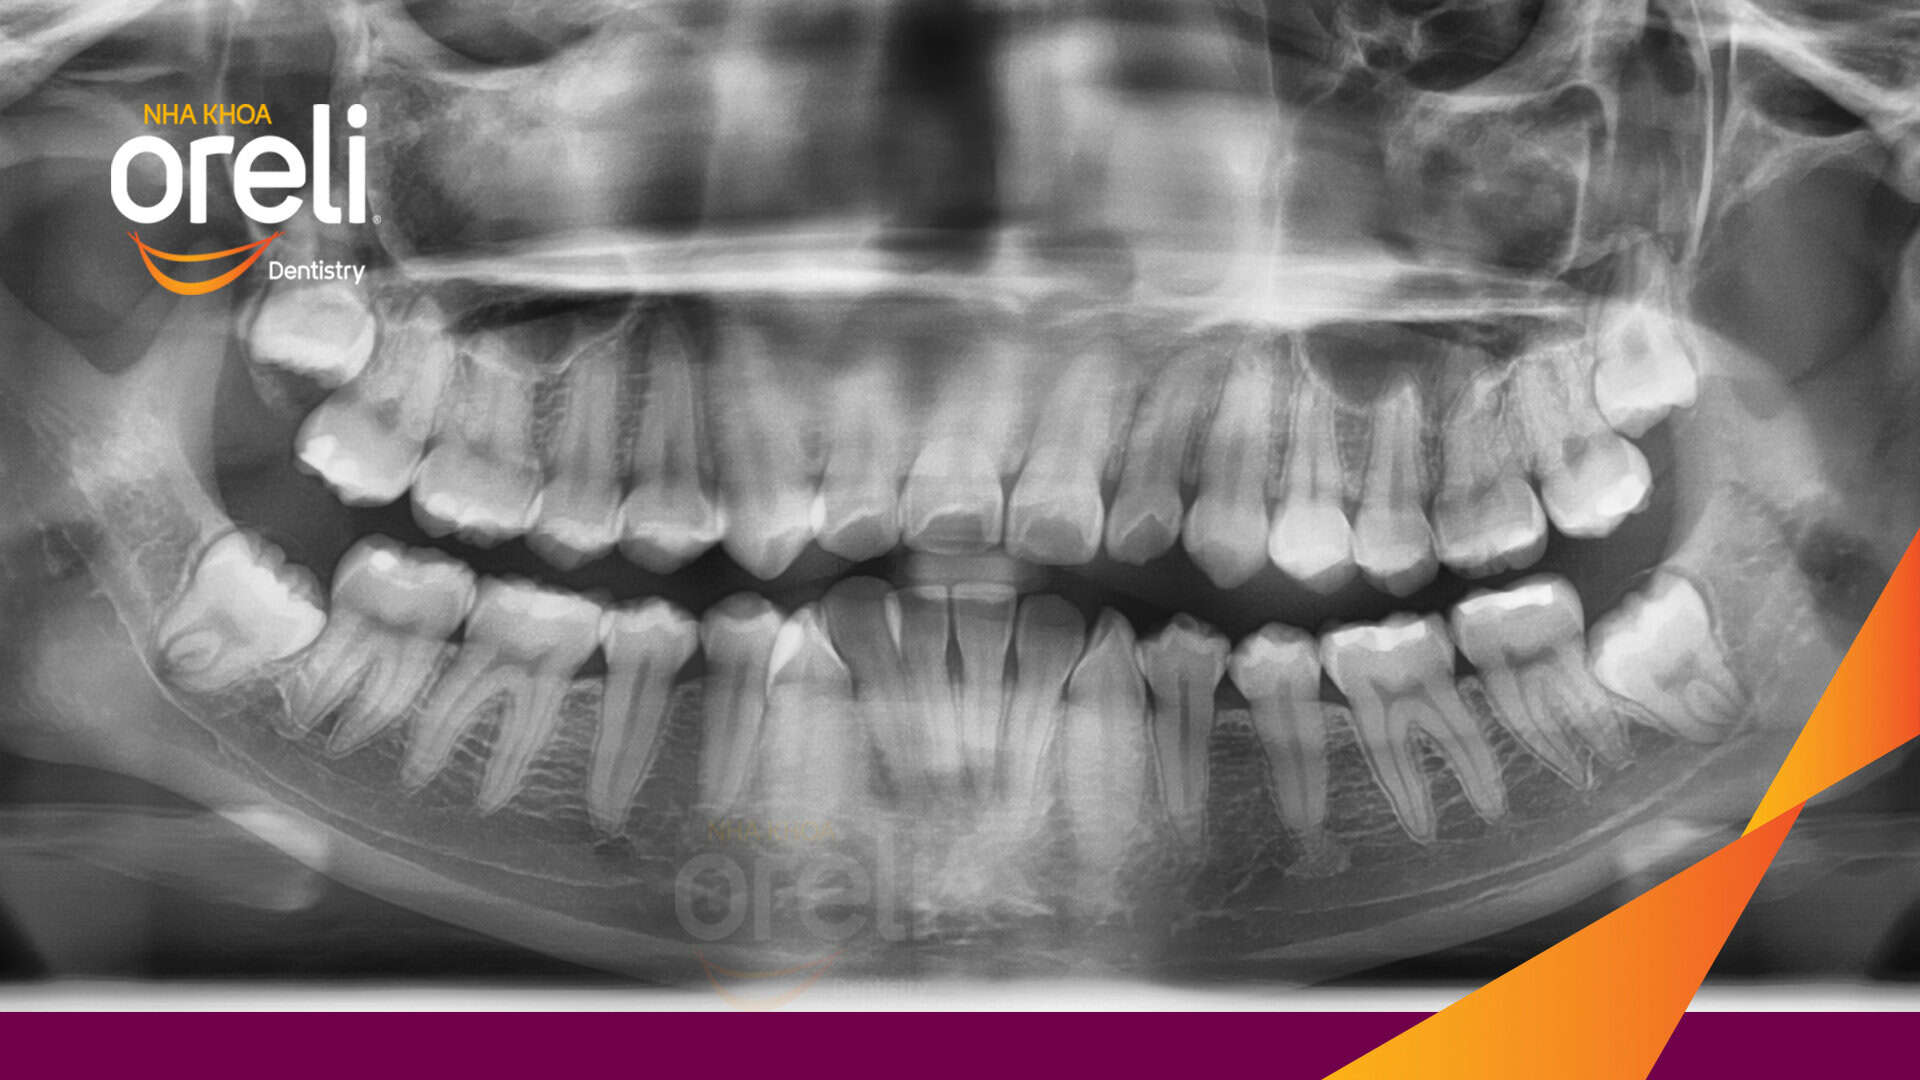

Tình trạng: Răng hô nhô xương ổ hai hàm

Giải pháp: Nhổ 4 răng số 4 niềng răng với măc cài kim loại

Trong trường hợp này độ nhô môi lớn, góc mũi môi nhọn, môi trên và dưới trượt ra trước so với đường thẩm mỹ E của Rickket, trục răng cửa hàm trên ngả trước nhiều. Việc nhổ răng 4 để giảm hô được thực hiện.